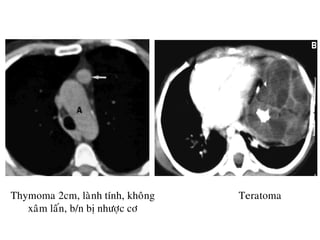

-U: Thymoma, Teratoma, Thyroid, Lymphoma

Thymoma 2cm, laønh tính, khoâng

xaâm laán, b/n bò nhöôïc cô

Teratoma